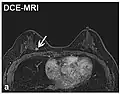

| Dynamic contrast enhanced | DCE | Measures changes over time in the shortening of the spin–lattice relaxation (T1) induced by a gadolinium contrast bolus.[76] | Faster Gd contrast uptake along with other features is suggestive of malignancy (pictured).[77] |

| |